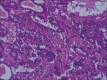

Salivary gland swellings can result from tumors, an inflammatory process or cysts. It can sometimes be difficult to establish; whether pathology arises from the salivary gland itself or adjacent structures. Neoplasms of the salivary glands account for less than 1% of all tumors, 3-5% of all head and neck tumors and benign pleomorphic adenoma (PA) of minor salivary glands arising de novo is very rare. PA is the most common tumor of the salivary gland. While the majority arises from the parotid gland, only a small percentage arises from the buccal minor salivary gland. A case of PA of minor salivary glands in the buccal mucosa in a 70-year-old female is discussed. It includes review of literature, clinical features, histopathology, radiological findings and treatment of the tumor; with emphasis on diagnosis.

Keywords: Buccal minor salivary gland; chondromyxoid stroma; pleomorphic adenoma.